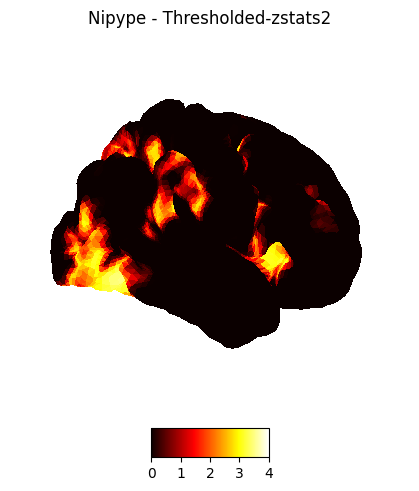

The first-level GLM#

Here we randomly choose the four copes from subject-09 run-1

nipype_cope1 = './output_level1/level1_results/09/results_dir/_subject_id_09/_level1estimate0/results/cope1.nii.gz'

nipype_cope2 = './output_level1/level1_results/09/results_dir/_subject_id_09/_level1estimate0/results/cope2.nii.gz'

nipype_cope3 = './output_level1/level1_results/09/results_dir/_subject_id_09/_level1estimate0/results/cope3.nii.gz'

nipype_cope4 = './output_level1/level1_results/09/results_dir/_subject_id_09/_level1estimate0/results/cope4.nii.gz'

plotting.plot_stat_map(nipype_cope1, bg_img=nipype_cope1, title = 'Nipype - COPE1', cmap = 'bwr', colorbar = False)

plt.show()

plotting.plot_stat_map(nipype_cope2, bg_img=nipype_cope1, title = 'Nipype - COPE2', cmap = 'bwr', colorbar = False)

plotting.plot_stat_map(nipype_cope3, bg_img=nipype_cope1, title = 'Nipype - COPE3', cmap = 'bwr', colorbar = False)

plotting.plot_stat_map(nipype_cope4, bg_img=nipype_cope1, title = 'Nipype - COPE4', cmap = 'bwr', colorbar = False)

../../_images/a7f7f387884673a96e62aa7d2d938a6b6487846759bc4500b6d0cff677c7358d.png ../../_images/bc743ce13891ebab23c9f6c7d4d668db8d11c9409d4f6e4580f7d63b35ecdb77.png ../../_images/228b3b22c00177a8ad5dc1793cbbc90dbfb495735196a4af47e73b899de0ca82.png ../../_images/babe8f68f0856f0f1608dfe550483d8ca862aae33a659d1f970a9fbe726f3bb1.png